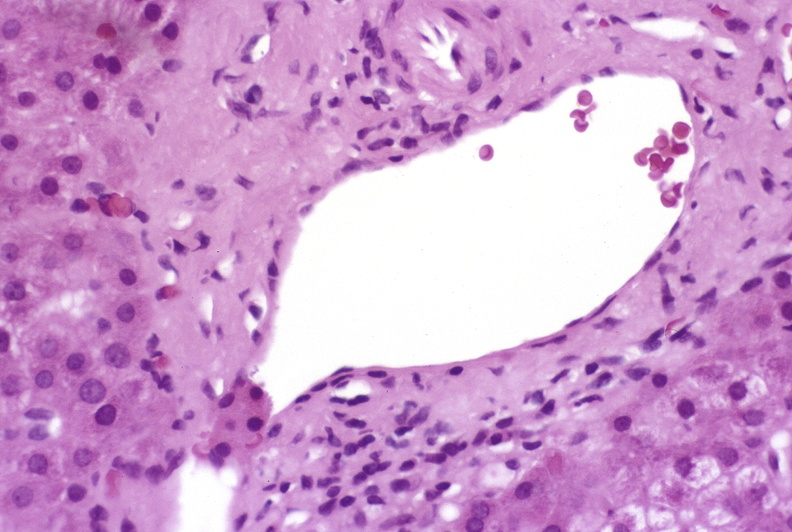

Refer to caption

Question: Identify the system or structure that is present in the image.

Thought Process: The image appears to be a histological section of tissue, likely from an organ such as the liver or pancreas, given the presence of acinar structures and ducts. The pinkish hue is typical of hematoxylin and eosin (H&E) staining used in pathology for distinguishing different types of cells and tissues. The presence of acini suggests that this could be part of the endocrine or exocrine pancreatic tissue, where acini are responsible for producing enzymes and hormones. However, without more specific details like the shape of the ducts, the size of the acini, or other characteristic features, it’s challenging to pinpoint the exact system or structure. Given the context provided by the image, we can infer that it might be related to the digestive system due to the presence of duct-like structures, which are common in organs like the pancreas and liver. Therefore, based on the visual clues and the typical uses of H&E staining in pathology, the most likely system or structure present in the image is the gastrointestinal (GI) tract.

Answer: Hepatobiliary.

Figure 11: Qualitative Result Example 4